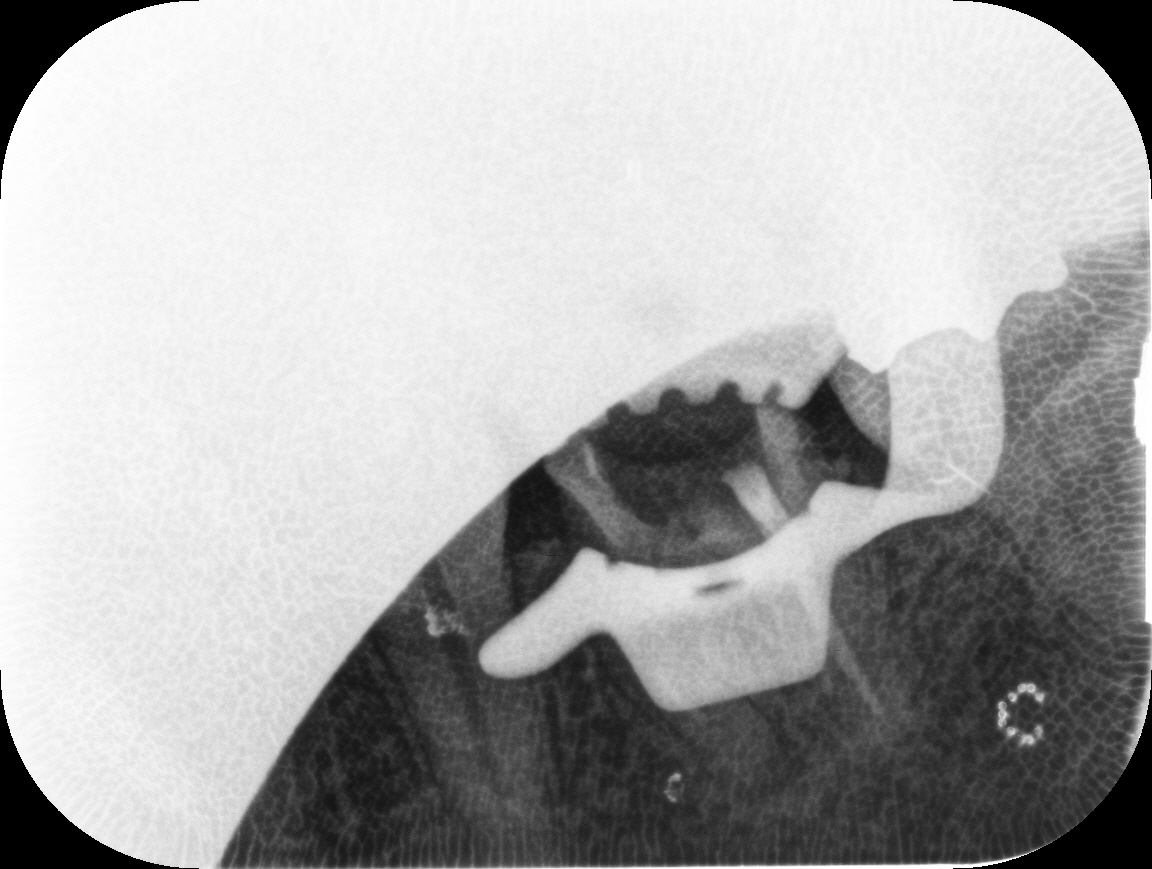

こちらは根管治療の途中のものなのですが、根の先に黒い病気があるのと、

根の途中にぐるぐるしたものがあります。

実はこれは治療用の器具が折れて残ってしまったものです。

えっ!って思うでしょうが、非常に細い器具で、根の形も複雑なので

起こってしまうときは、起こります。

なので、論文でもありました。しっかりと感染源が除去できていれば(ここが重要です!)

治療の成功率には影響ないそうです。

根の治療です!

無事に除去で来ました!

比較できるように並べてみました。

ねじねじしたものが除去できたのが、わかりますかね?

もちろん簡単な処置ではないですし、マイクロスコープを使って時間もかかりました。

これができないと外科的な治療になったり、最悪歯を抜くことになります。

歯を残せるように、僕も患者さんも頑張りました!(口を長く開けているのは苦痛ですもん)